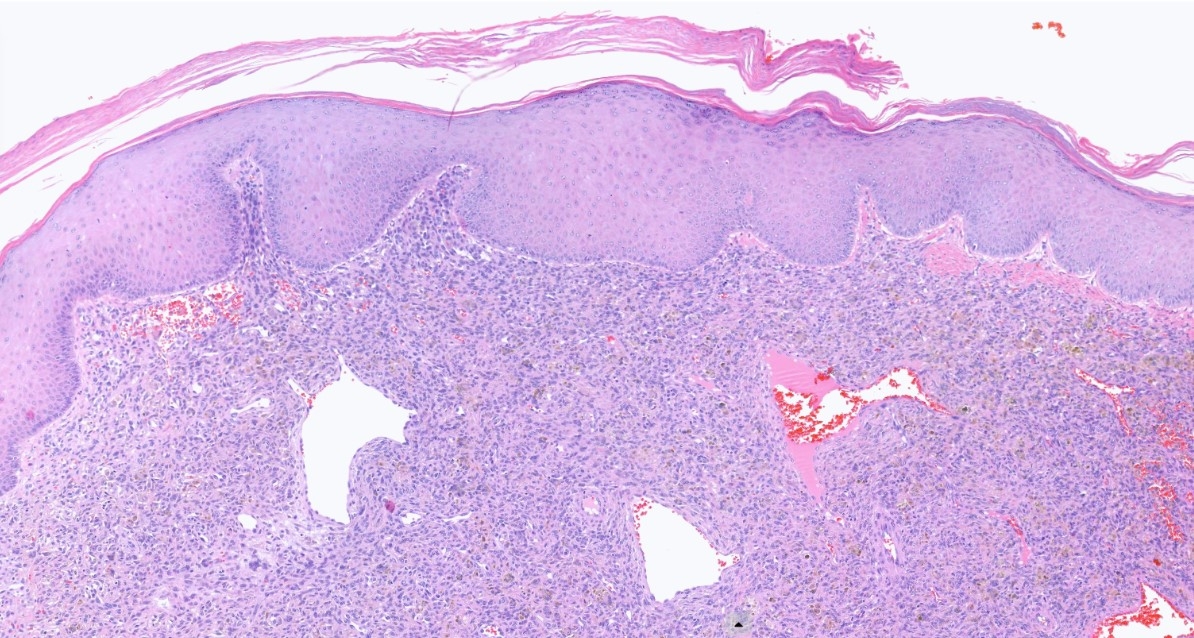

16M, Back-Excision ? Angioma